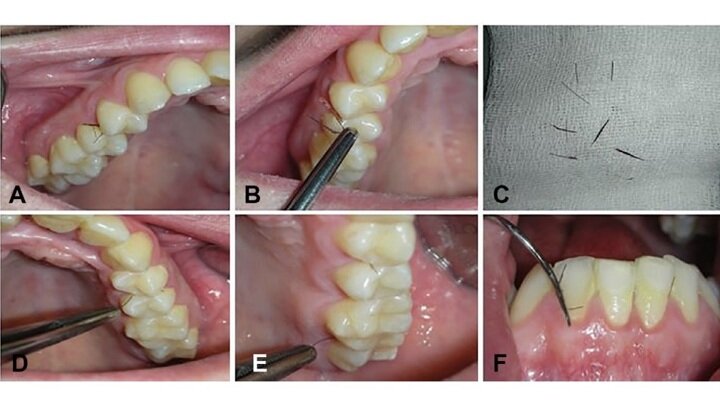

Появление волосков в полости рта - чрезвычайно редкое явление, его причины до сих пор точно неизвестны.Фото Zhurakivska, et al., Oral Surgery, Oral Medicine, Oral Pathology and Oral Radiology, 2020.

Пациентке удалили волосы во рту, а также назначили курс оральных контрацептивов, чтобы устранить гормональный дисбаланс. Несколько месяцев спустя врачи не обнаружили никаких признаков роста новых волос.

Однако через шесть лет молодая женщина вновь обратилась в клинику. Она прекратила принимать гормоны, и гирсутизм дёсен вернулся. Более того, волосы также появились на подбородке и шее.

На этот раз врачи не только удалили волосы, но также взяли небольшой фрагмент ткани, чтобы изучить его. По их словам, ткань десны была необычайно утолщённой, и сквозь неё пробивался волосяной стержень.